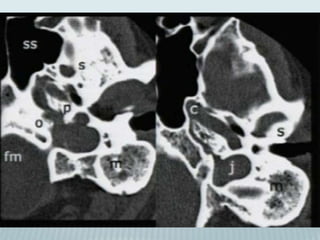

Petrous and its subsegments

•Pyramid and otic capsule

•Subsegments

1. Anterior

2. Posterior

3. Inferior

4. Apical

Anterior petrous subsegment

Tegmen tympani

Arcuate eminence

Prominence

over upper

SCC

Posterior petrous subsegment

Inner acoustic pore;

Inner ear canal joins SAS

Inferior petrous subsegment

•Carotid canal

•Jugular foramen